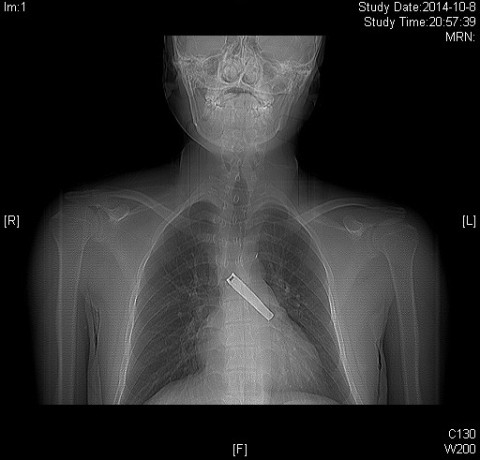

指甲钳压柄吸入气管 气管镜取出免开胸

近日,中山医院胸外科应用硬质气管镜成功将一例巨大支气管异物取出,使患者免除了开胸手术的痛苦和风险。年